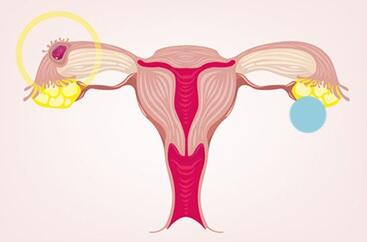

بارداری